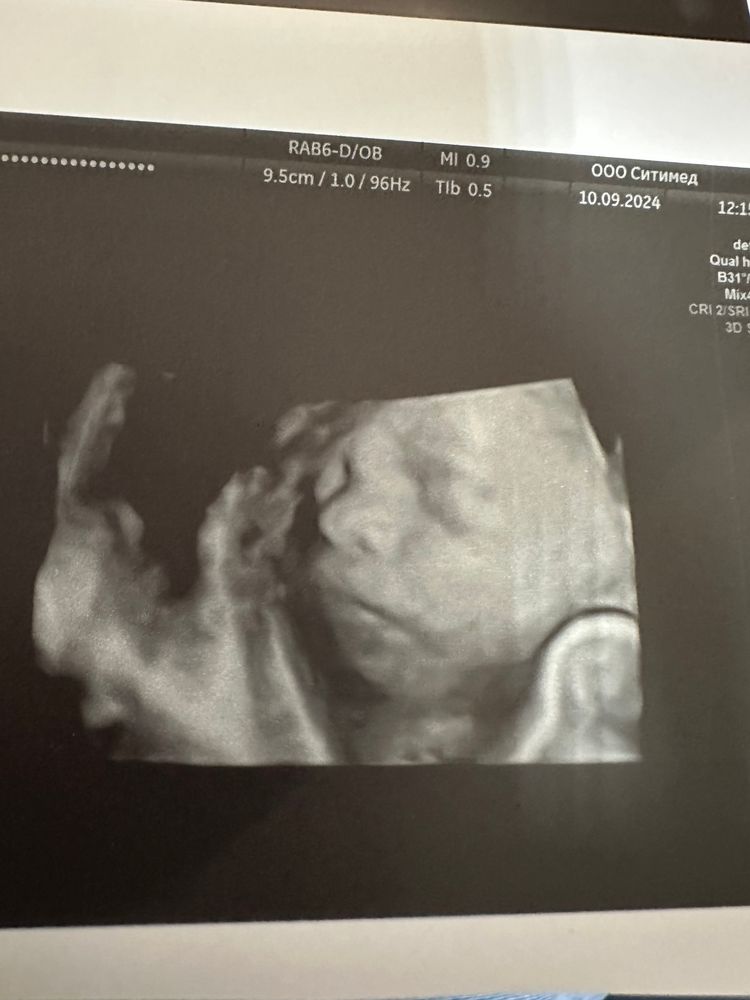

23/4 Нед узи

638 гр ЧСС 136, шустрый парень